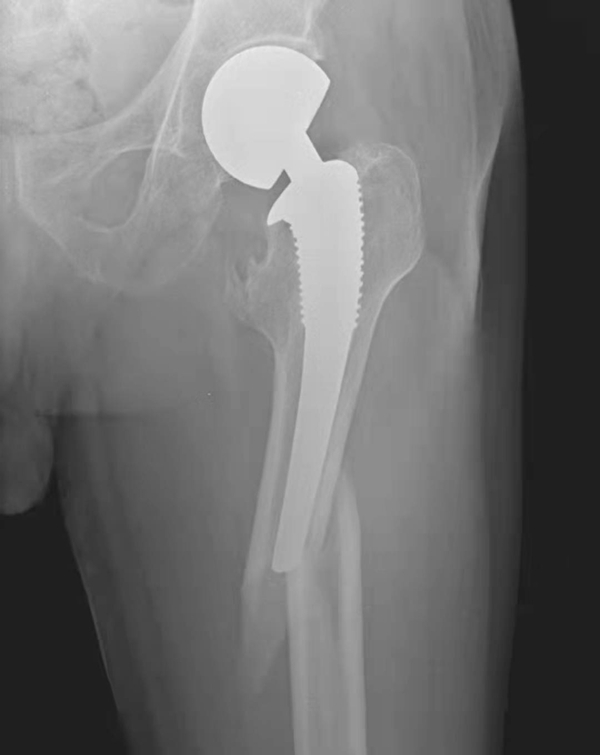

图1 人工髋关节置换术后正常X线表现